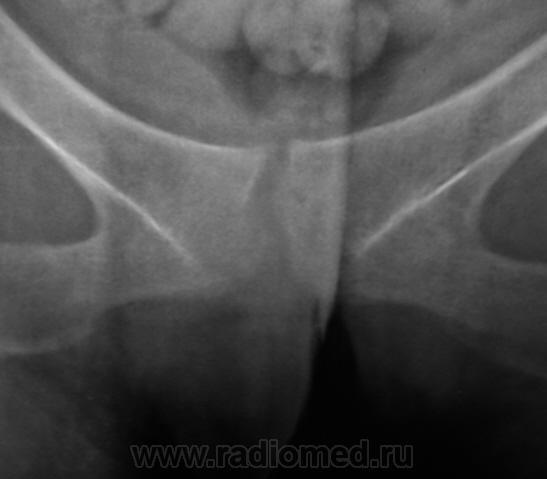

Из анамнеза известно, что примерно 2 месяца тому "летела" со сноутборга около 200 метров. Сейчас беспокоят боли в области спины, крестца и лонного сочленения. УЗИ было сделано всего, что только можно, везде - "норма". Хирурги, вроде-бы тоже ничего не находят. Но боли, видать значительные, походка вынужденная. На рентгенографию была направлена, как жест отчаяния, мол может быть, что-то найдут.

Так как "содержимое кишечника" не способствовало анализу изображений, пациентке было предложено, посетить кабинет повторно.

Рентгенограмма в прямой проекции.

1. Не исключаю поперечный перелом S5.

2. Лонное сочленение очевидно,подверглось значительному растяжению (имеется локальный вакуум-феномен слева), умеренно выраженые явления симфизита (опять же - постравматического).

1. По первым снимкам не отпускало впечатление о повреждении левого крестцово-подвздошного сочленения. После подготовки вроде-бы все нормально, но все равно что-то гложет.